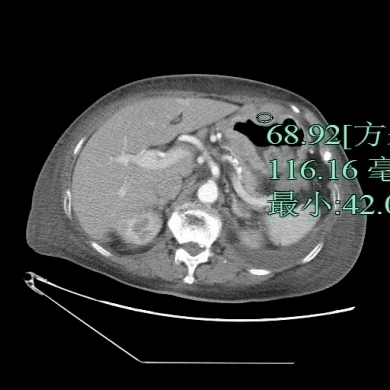

患者 , 女性 , 87岁 , 因咳嗽气急1周、发热4天入院 。 查体:未见明显异常 。 影像检查如下 , 以下哪个诊断最有可能?

文章图片

A.胃癌

B.肥厚性胃炎

C.淋巴瘤

D.神经内分泌肿瘤

E.间质瘤